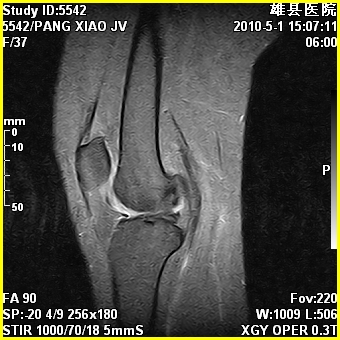

标题: MRI2894:患者右膝关节疼痛两月余,无明显外伤史 [打印本页]

标题: MRI2894:患者右膝关节疼痛两月余,无明显外伤史

右股骨下端前内侧类圆形异常信号,位于干骺端,呈长t1长t2改变,但信号不均,t1图上病灶中心见小片状稍高信号影,t2图上见散在稍低信号影,stir像呈高信号,因病灶较小,缺乏特征性改变,结合患者年龄及部位,考虑嗜酸性肉芽肿可能性大。胫骨关节面下的小囊状异常信号,如果一元论考虑则为嗜酸性肉芽肿,不过发生在这个部位的少见,二元论考虑为邻关节骨囊肿。半月板与前后交叉韧带均未见异常。

右股骨下端前内侧干骺端囊性良性病变,考虑 1内生软骨瘤 2骨囊肿 3肉芽肿。